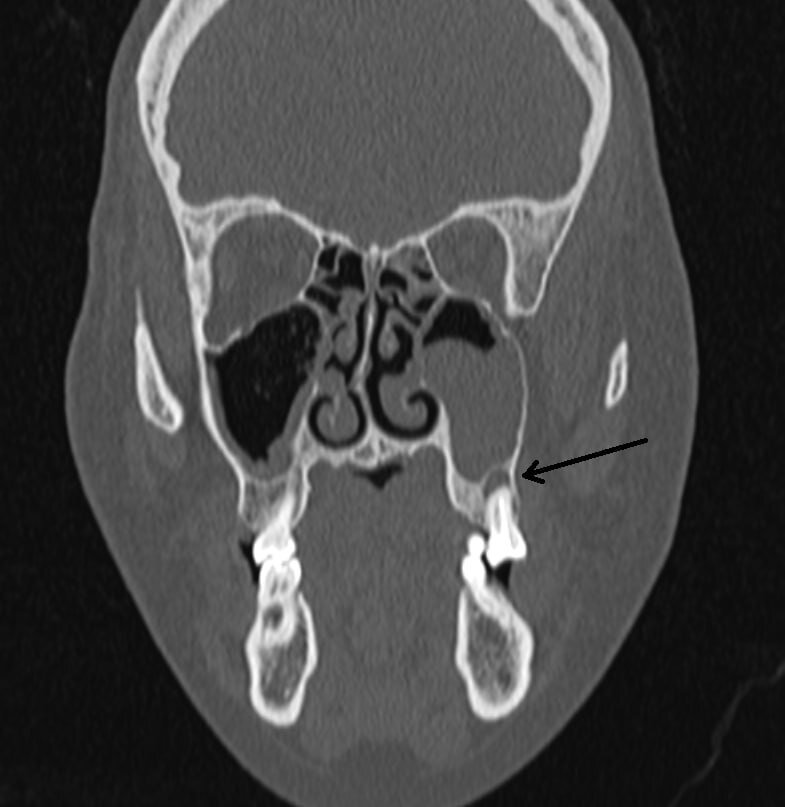

В кабинет компьютерной томографии медицинского центра "НовоМед" обратилась пациентка, 38 лет, жалуясь на постоянную заложенность носа в течение года. На МСКТ органов грудной клетки выявлена тотальная инфильтрация (воспаление) в левой верхнечелюстной пазухе, а также киста корня шестого зуба. Именно киста стала причиной постоянного воспаления пазухи (одонтогенного гайморита). В этот же день пациентку проконсультировал ЛОР-врач, который назначил соответствующее лечение. Для устранения первопричины данного состояния женщине рекомендована консультация стоматолога. Как зуб может быть связан с носом? Одонтогенный гайморит — воспаление гайморовых пазух, которое развивается от инфицированных зубов верхней челюсти. Проникновению инфекции также способствуют стоматологические манипуляции в области верхнечелюстных синусов — лечение и удаление зубов, имплантация и синус-лифтинг. Без выявления и устранения причины стандартное лечение у ЛОР врача в поликлинике не приносит результатов. Без должног